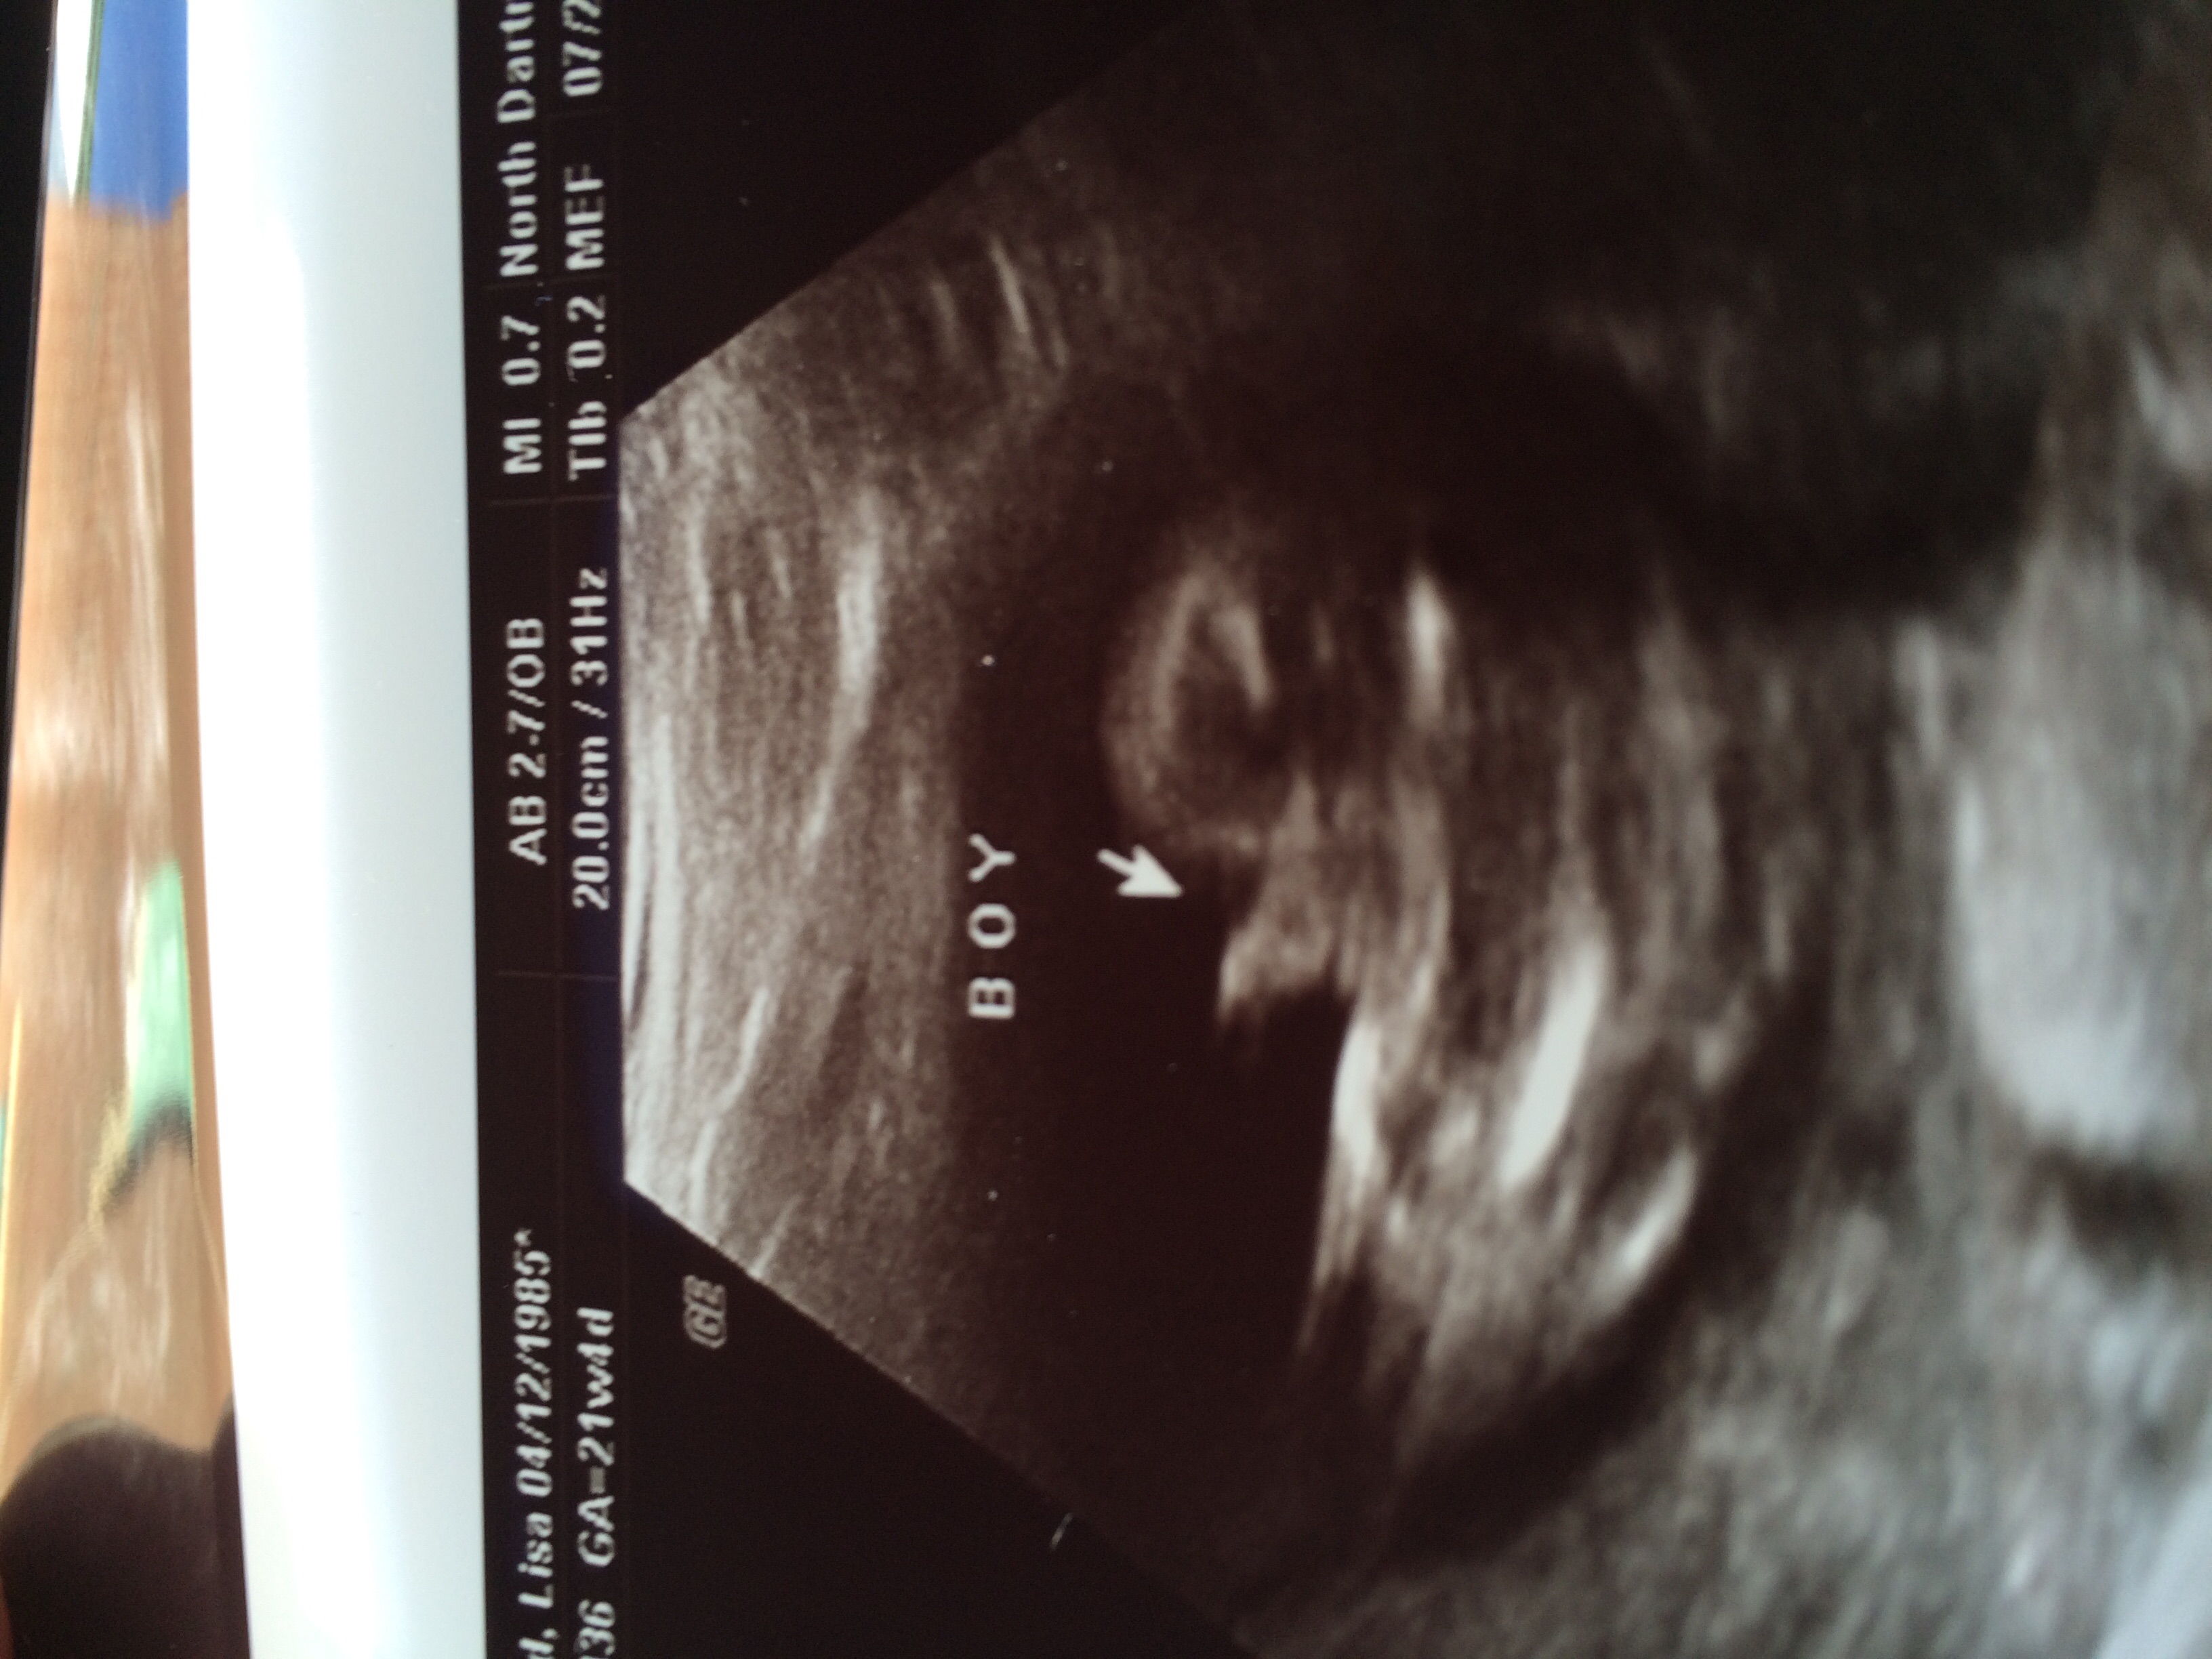

We found out today we are having a bouncing baby boy! Unfortunately I won't know if he's healthy until the doctor calls me later today or tomorrow because she was rushed into delivery. I have heard horror stories about mommies finding out they are really having girls in the delivery room so now it's stuck in my head. Opinions??? The tech seemed VERY convinced he is a he but I need an extra push.

• I would trust your tech. This is one of the many things they are trained for. I am having a boy and the picture I was given is very similar to what you have. The picture is zoomed in and will look bigger then it actually is especially since baby is still pretty tiny (a pound or less). My little guy was only 11 ounces at the time of my ultrasound yet looks huge in most pictures.

• moweltmowelt member

I am having a boy and my sonogram looked just like that. Also it was confirmed by 2 different ultrasound techs at different places and both looked like that. My tech said she knew from a different angle and then moved to that angle for the one to print out for me to prove it was a boy. Your tech knows what they are doing and to me that is definitely a boy.

• Will they do another U/S at any point? If not there's always the 4D one, Its pricey but it might help with a for sure answer. I found out I'm having a boy too but they gave me a different angle its between the legs so the penis looks different, but I'm sure its just the angle.

I would trust your tech more than anyone on this board with no medical background (no offense ladies ;) ) Mine looked just like this and were having a boy. Our tech also mentioned something about seeing through the cord and not a penis, or vice versa, I don't quite remember. If your still unsure, I would ask your doctor before doing an unnecessary scan.

thats probably partially umbilical cord, but your tech was able to tell more than we can by his little pelvic bump, girls are suppose to have a flat pelvic area while boys have a "turtle shell", and depending on the angle of the picture is whether the little turtle has a head or not.